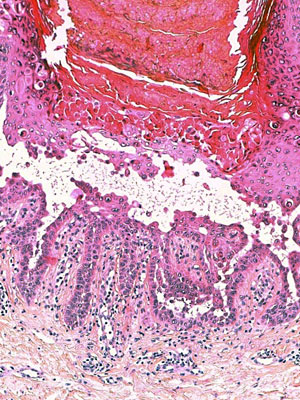

Le diagnostic s’établit sur des images, visualisées au microscope, de prélèvements cellulaires (biopsies, organes ou fragments d’organes, frottis, ponction de liquide).

Afin que les prélèvements soient visualisables au microscope, les techniciens du cabinet de pathologie vont réaliser sur ceux-ci des coupes ultra-fines, secondairement colorées puis mises sur lame de verre.

Le médecin va ensuite visualiser la lame et poser un diagnostic.